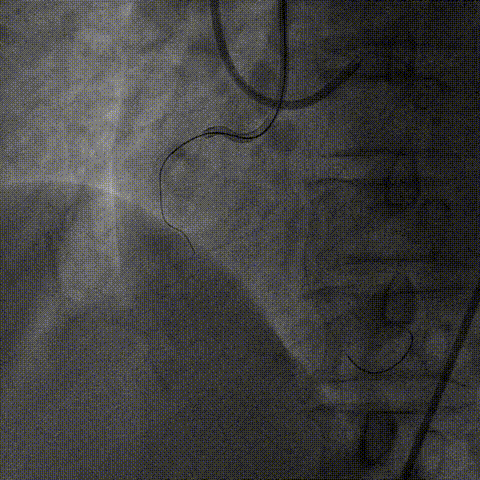

1、正向导丝通过后,微导管无法跟进,尝试1.25、1.5mm球囊均无法通过病变。

2、6F Telescope™导引延长导管支撑下1.25mm球囊通过病变预扩后换用2.0mm球囊完成预扩张。

1、2.0mm球囊预扩张后球囊顺利进入Telescope™导引延长导管锚定导丝,送入Finecross微导管,后交换Pilot200导丝为Runthrough导丝。

2、6F Telescope™导引延长导管可兼容2号2.0mm预扩球囊及Finecross微导管同时进入,具有良好的内腔兼容性。

2.0mm球囊进入Telescope™锚定,通过无阻力

2.0mm球囊锚定导丝后微导管进入Telescope™内腔兼容性强